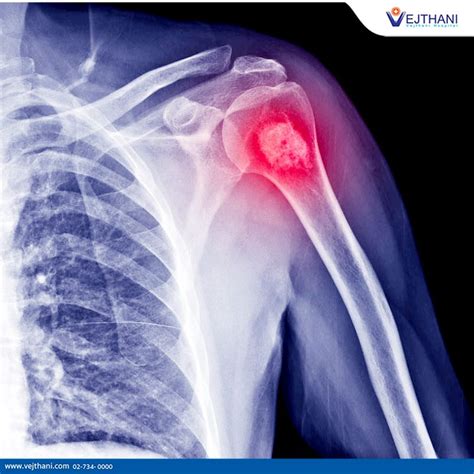

Imaging plays a huge role in the diagnosis of osteosarcoma , acting as our eyes to see what’s happening inside the body. X-rays are often the very first step. They’re readily available and can quickly show us if there’s something unusual going on in the bone – maybe a lesion that’s eating away at the bone, or a new, dense area forming. They can reveal classic signs like the Codman’s triangle (a small piece of bone lifted off the periosteum, the outer layer of bone, due to the tumor pushing it up) or the sunburst pattern (spicules of bone radiating outwards). However, X-rays have their limitations. To get a more detailed view, CT scans are crucial. They provide cross-sectional images, giving us a fantastic look at the bone’s internal structure and allowing us to see if there’s any calcification within the tumor. CT scans are also the go-to for checking if the cancer has spread to the lungs, which is a common site for metastasis. Then there’s MRI , which is often considered the best imaging modality for osteosarcoma of the limbs. MRI excels at showing the soft tissues. It gives us a detailed map of the tumor’s size, its precise location, and how far it has invaded into the surrounding muscles, nerves, and blood vessels. This information is critical for surgeons when planning how to remove the tumor. Think of it as providing the blueprint for the operation. Lastly, bone scans are useful for detecting if the cancer has spread to other bones in the body. They work by injecting a small amount of radioactive material that is taken up by areas of increased bone activity, like cancerous growths. Together, these imaging techniques paint a comprehensive picture, guiding the medical team towards an accurate diagnosis and a tailored treatment strategy. They help us understand the scope of the problem before we even consider a biopsy.

Okay, so someone’s experiencing symptoms, and they go to the doctor. What happens next? This is where the diagnosis of osteosarcoma kicks in, and it’s a bit like being a medical detective. The first step usually involves a thorough physical examination and a detailed discussion about your symptoms and medical history. The doctor will want to know about the pain, swelling, and any other changes you’ve noticed. Then comes the imaging. X-rays are often the first line of imaging when bone pain or swelling is reported. They can reveal abnormalities within the bone, such as a lytic lesion (where bone is destroyed), a sclerotic lesion (where bone is abnormally dense), or a combination of both. They can also show if the bone has been weakened or fractured. However, X-rays alone aren’t always definitive for osteosarcoma. To get a clearer picture and to assess the extent of the tumor, CT scans (Computed Tomography) and MRI scans (Magnetic Resonance Imaging) are typically ordered. CT scans are excellent for looking at the bone structure and detecting any calcifications within the tumor, and they are also used to check for metastasis to the lungs. MRI scans are particularly useful for visualizing the soft tissues surrounding the tumor and determining its exact size and boundaries, which is crucial for surgical planning. To confirm the diagnosis and determine the specific type of cancer, a biopsy is absolutely essential. This is the gold standard. A small sample of the tumor tissue is removed, either through a needle biopsy or a surgical procedure, and examined by a pathologist under a microscope. The pathologist looks for characteristic features of osteosarcoma, such as the production of osteoid by malignant cells. The biopsy not only confirms that it is osteosarcoma but also helps determine its grade (how aggressive the cancer cells appear). Sometimes, bone scans (nuclear medicine scans) are used to see if the cancer has spread to other bones. And finally, blood tests, including alkaline phosphatase levels, might be done as these can sometimes be elevated in patients with osteosarcoma. The combination of these diagnostic tools allows doctors to build a complete picture of the disease.